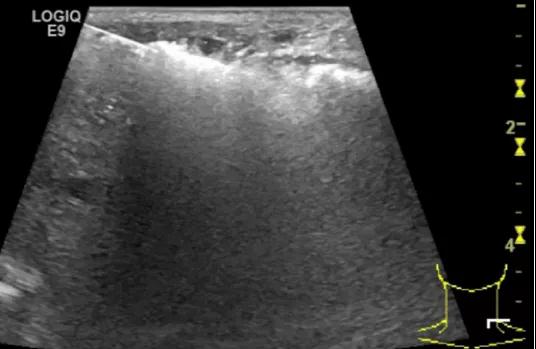

随后,徐栋教授进一步分享了五个临床实战病例,带来了更直观的热消融治疗经验。第一个病例是62岁肺癌患者,术后1年余发现双侧锁骨上淋巴结复发,侵犯神经,存在静脉回流、淋巴回流障碍,肿胀、疼痛非常明显。影像显示患者淋巴结边界不清、形态不规则,存在浸润,血流强化增强。由于患者在系统治疗后进展,且主要目的缓解症状、减瘤。局麻下行热消融术,从后向前逐层消融,热消融之后超声造影即刻评估显示完全充盈缺损,完全覆盖病灶。

(病例1图例)